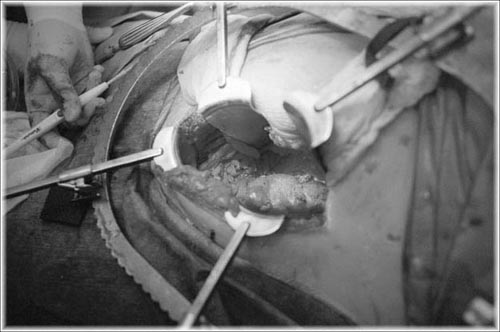

Bob's new kidney moments after reattachment.